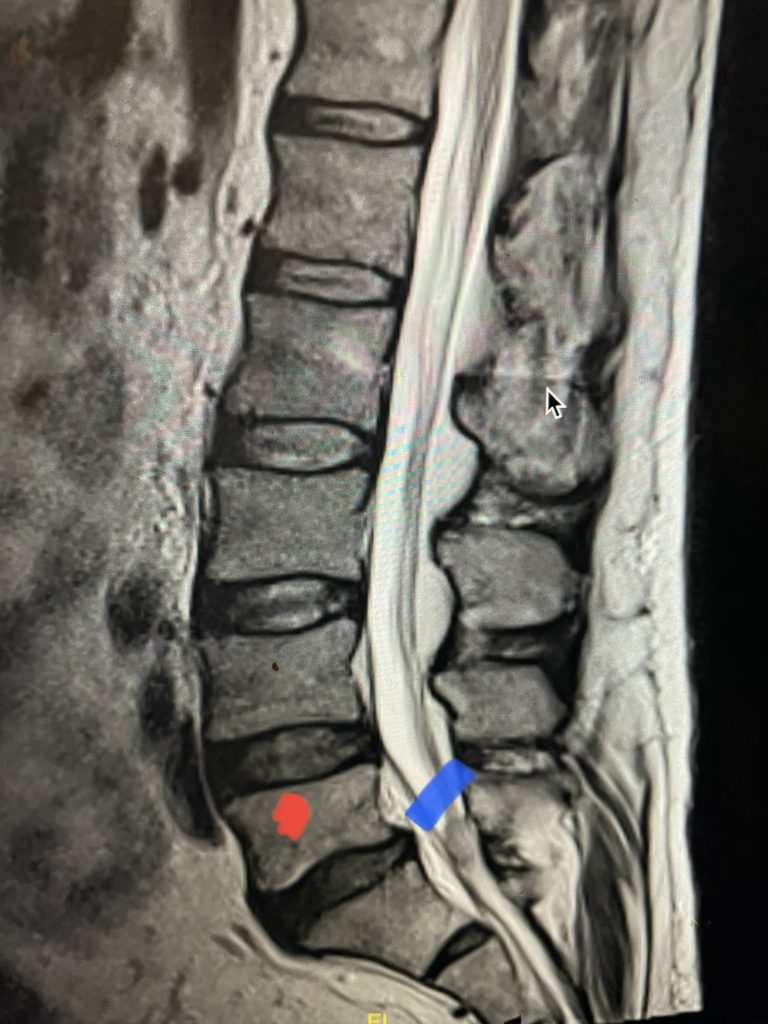

Fig 2: Sagittal T2-weighted MRI of the lumbar spine demonstrating a dysmorphic, trapezoidal-shaped L5 vertebral body (red dot) and a subtle grade 1 spondylolisthesis L5-S1 (blue line).

Another interesting 54-year-old patient presented with low back pain and severe left lower extremity pain over two months. He had a history of falls. The pain in the leg was more bothersome to the patient. The patient had a work-up with an MRI and CT of the lumbar spine. MRI demonstrated a subtle grade 1 spondylolisthesis L5-S1 with a dysmorphic L5 vertebral body (Fig 2). There was a suggestion of a left L5 spondylolysis or defect in the bridge of bone that connects the superior facet process of the segment and the inferior facet process. A CT of the lumbar confirmed this unilateral abnormality which certainly could account for the patient’s left leg pain (Fig 3). This is an unusual finding in that most patients have bilateral pars defects. Patients with L5-S1 often have congenital abnormalities of the lumbosacral junction including weird shaped, elongated or dysplastic facet joints. A subtle L5-S1 spondylolisthesis with an associated smaller and misshapen L5 vertebral body is often associated with L5 spondylolysis. In addition, with a dysmorphic L5 vertebral body, there is secondary disc degeneration at L5-S1 and sometimes at the L4-5 disc with an associated retrolisthesis at L4-5. There is less surface to surface contact of the L4-5 and L5-S1 leading to chronic segmental instability.